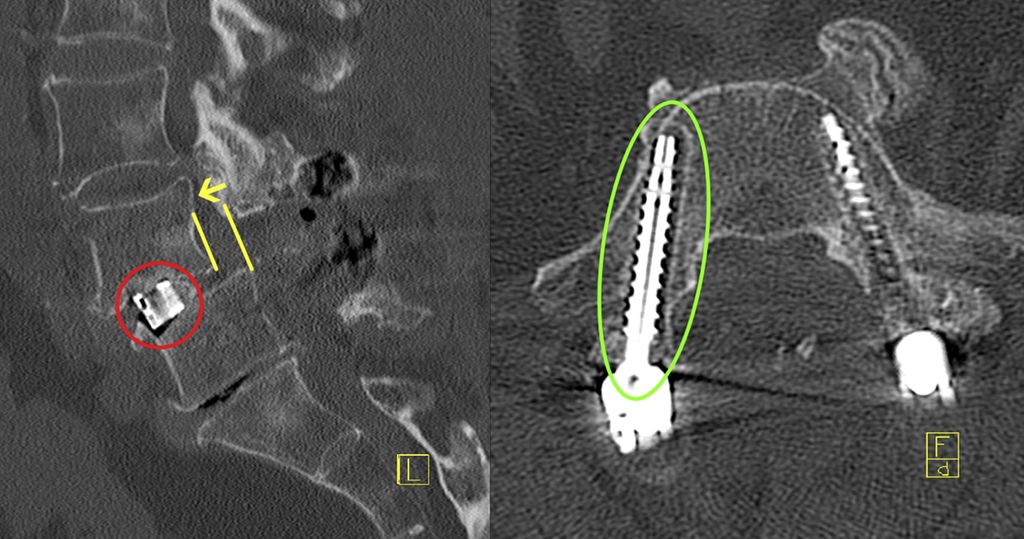

Durch den reduzierten Knochenumbau bei osteoporotischen Patient:innen kommt es auch zu einer verlangsamten knöchernen Fusion, wodurch nicht nur die Risiken für Schraubenlockerungen, sondern auch für Cage-Sinterung (Abb. 2) und Anschlussfrakturen erhöht sind.4, 21 Ein klarer Vorteil für ein bestimmtes Cage-Material dürfte nicht vorliegen. Cages aus Polyetheretherketon (PEEK) oder 3D-Druck versuchen, das Elastizitätsmodell des Wirbelkörpers zu spiegeln. Manche Studien deuten darauf hin, dass reine Titanimplantate eine höhere Sinterungsrate aufweisen als Implantate aus PEEK oder 3D-Druck.25 Viel mehr scheint die Implantatpositionierung und -größe eine Rolle zu spielen. Je mehr Kontakt zur Endplatte besteht, d.h., je größer das Implantat ist und je satter es anliegt, desto eher werden Druckspitzen vermieden und damit das Risiko für Sinterung reduziert.26

Abb. 2: Erhöhtes Risiko für Cage-Sinterung und Anschlussfrakturen durch reduzierten Knochenumbau